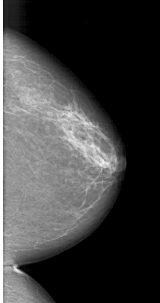

A_1415_1.LEFT_MLO

LEFT_MLO LINES 6316 PIXELS_PER_LINE 3151 BITS_PER_PIXEL 12 RESOLUTION 43.5 OVERLAY